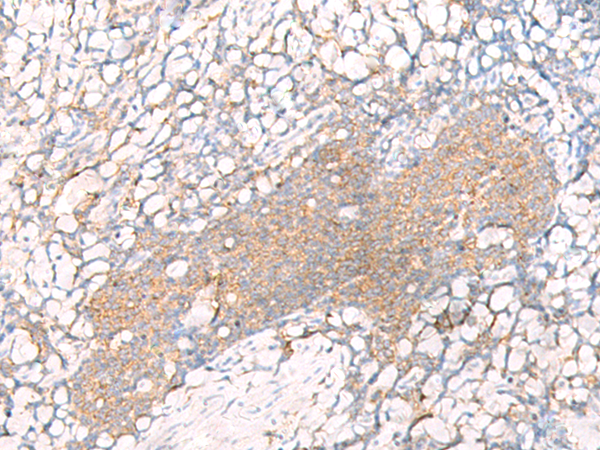

IHC positive control:

Human tonsil

IHC Recommend dilution:

20-100